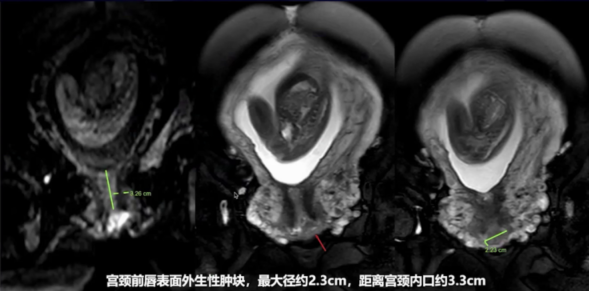

盆腔MRI:宫颈外口异常信号灶2.4cm×1.1cm,考虑MT。双侧附件内膜样囊肿可能(右4cm,左2cm)

宫颈科进行阴道镜检查评估,病灶局限在宫颈,大小约2.5cm,表面厚醋白上皮,表面轮廓不规则,见异型血管。舟状窝、会阴后联合见中厚醋白上皮,考虑低级别病变,后联合病灶活检送病理检查(后续病理提示未见明显癌灶或其他病变)。